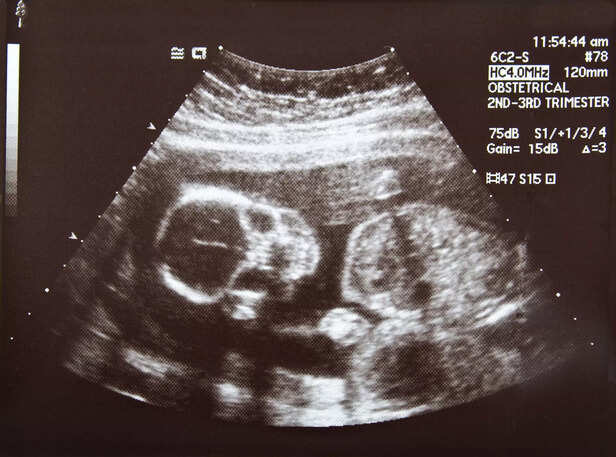

b. Diagnostic Evaluation

woman ultrasound

Diagnostic tools such as ultrasound imaging, fetal monitoring, and laboratory tests are utilized to confirm the diagnosis of placental abruption. Quick and accurate diagnosis is crucial for initiating appropriate management and minimizing complications.